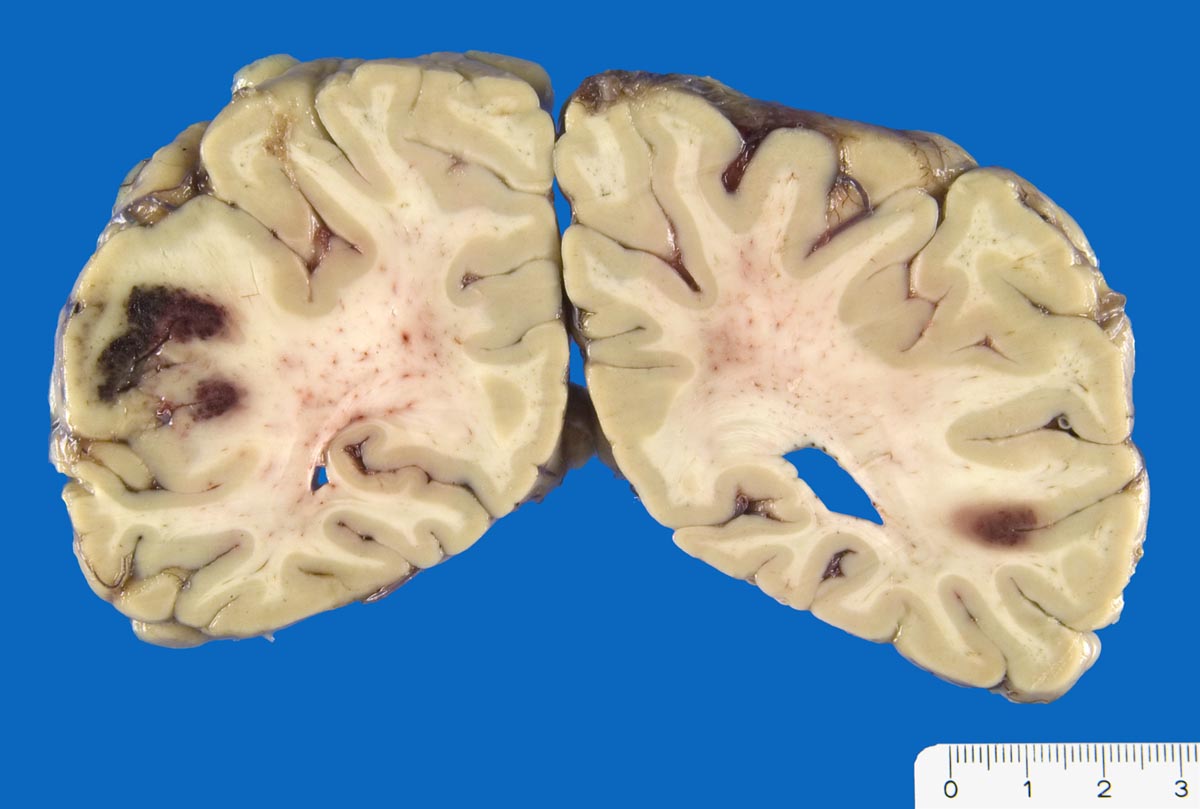

PathoPic ID 9875 - Sekundär hämorrhagische Enzephalomalazie

Sekundär hämorrhagische Enzephalomalazie

vaskulär / Durchblutungsstörung

Hirn

Nervensystem

Nicht ganz frische anämische Infarkte mit sekundärer Einblutung.

Arterielle Hypertonie. V.a. ischämischen Insult. Akutes Delir. CCT: links posteriore Hypodensität, kein Hemisyndrom

Koronare Herzkrankheit, St.n. Myokardinfarkt vor 11 Jahren.

Plötzlicher Tod

Makroskopie

83

männlich